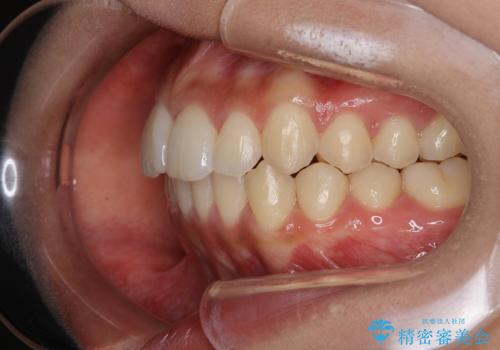

インビザライン矯正 短期間で出っ歯を改善

- 前歯が前に出ていることが気になるとのことで来院されました。

上顎の前歯が一本、唇側出ていることで、口元の突出があると感じているとのことでした。

奥歯の咬み合わせは特に問題がなかったため、上下顎の前歯のがたつきを、歯の側面を削ることで改善する治療計画としました。

この症例の患者様は、口元の突出感が気になるとのことでしたが、歯を抜く必要性がないと判断し、歯を抜かずに治療を行いました。前歯の角度を改善することで、口元が気にならなくなったと満足いただけました。